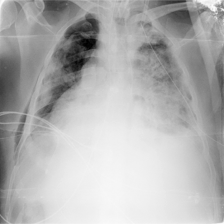

| Raw image | GT | Swin UNETR | nnU-Net | LViT | GuideDecode | MMI-UNet | Ours |

As shown in Table I, our SSA framework achieves state-of-the-art (SOTA) performance on both datasets. On QaTa-COV19, SSA achieves a Dice score of 91.65%, significantly outperforming the previous SOTA method (MLMoE, 91.19%). This demonstrates the effectiveness of our DSOT and CDG. The superior performance on MosMedData+ further validates the generalization capability of our approach. The qualitative results in Fig. 3 demonstrate that our model accurately segments infected areas while suppressing irrelevant regions.